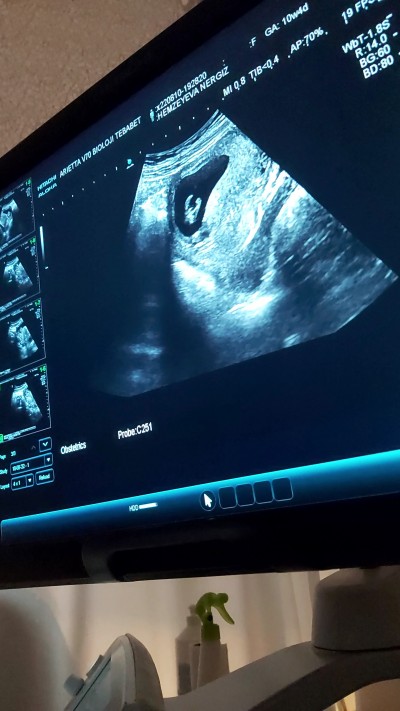

merhaba kizlar. 10+4 hafta nub teorisinden anlayanlar baka bilir mi. net'den araştırdım, dikey olunca erkek, yatay olunca kız yazıyor. ama benimkinde her pozisyona göre değişik. bazı resimlerde yatay, bazılarında dikey görünüyor. kendi doktorum izne çıktı ay sonu döner,

kalp atışı kontrolu için en yakın hastanede baktırdım. cinsiyet belli olmaz diyordum ama doktor 90% erkek benziyor dedi. tabi ne kadar tecrübeli doktor bilemiyorum. yatay pozisyonlar da aklımı karıştırdı eve gelince. kız gibi de duruyor sanki. bi bakar mısınız